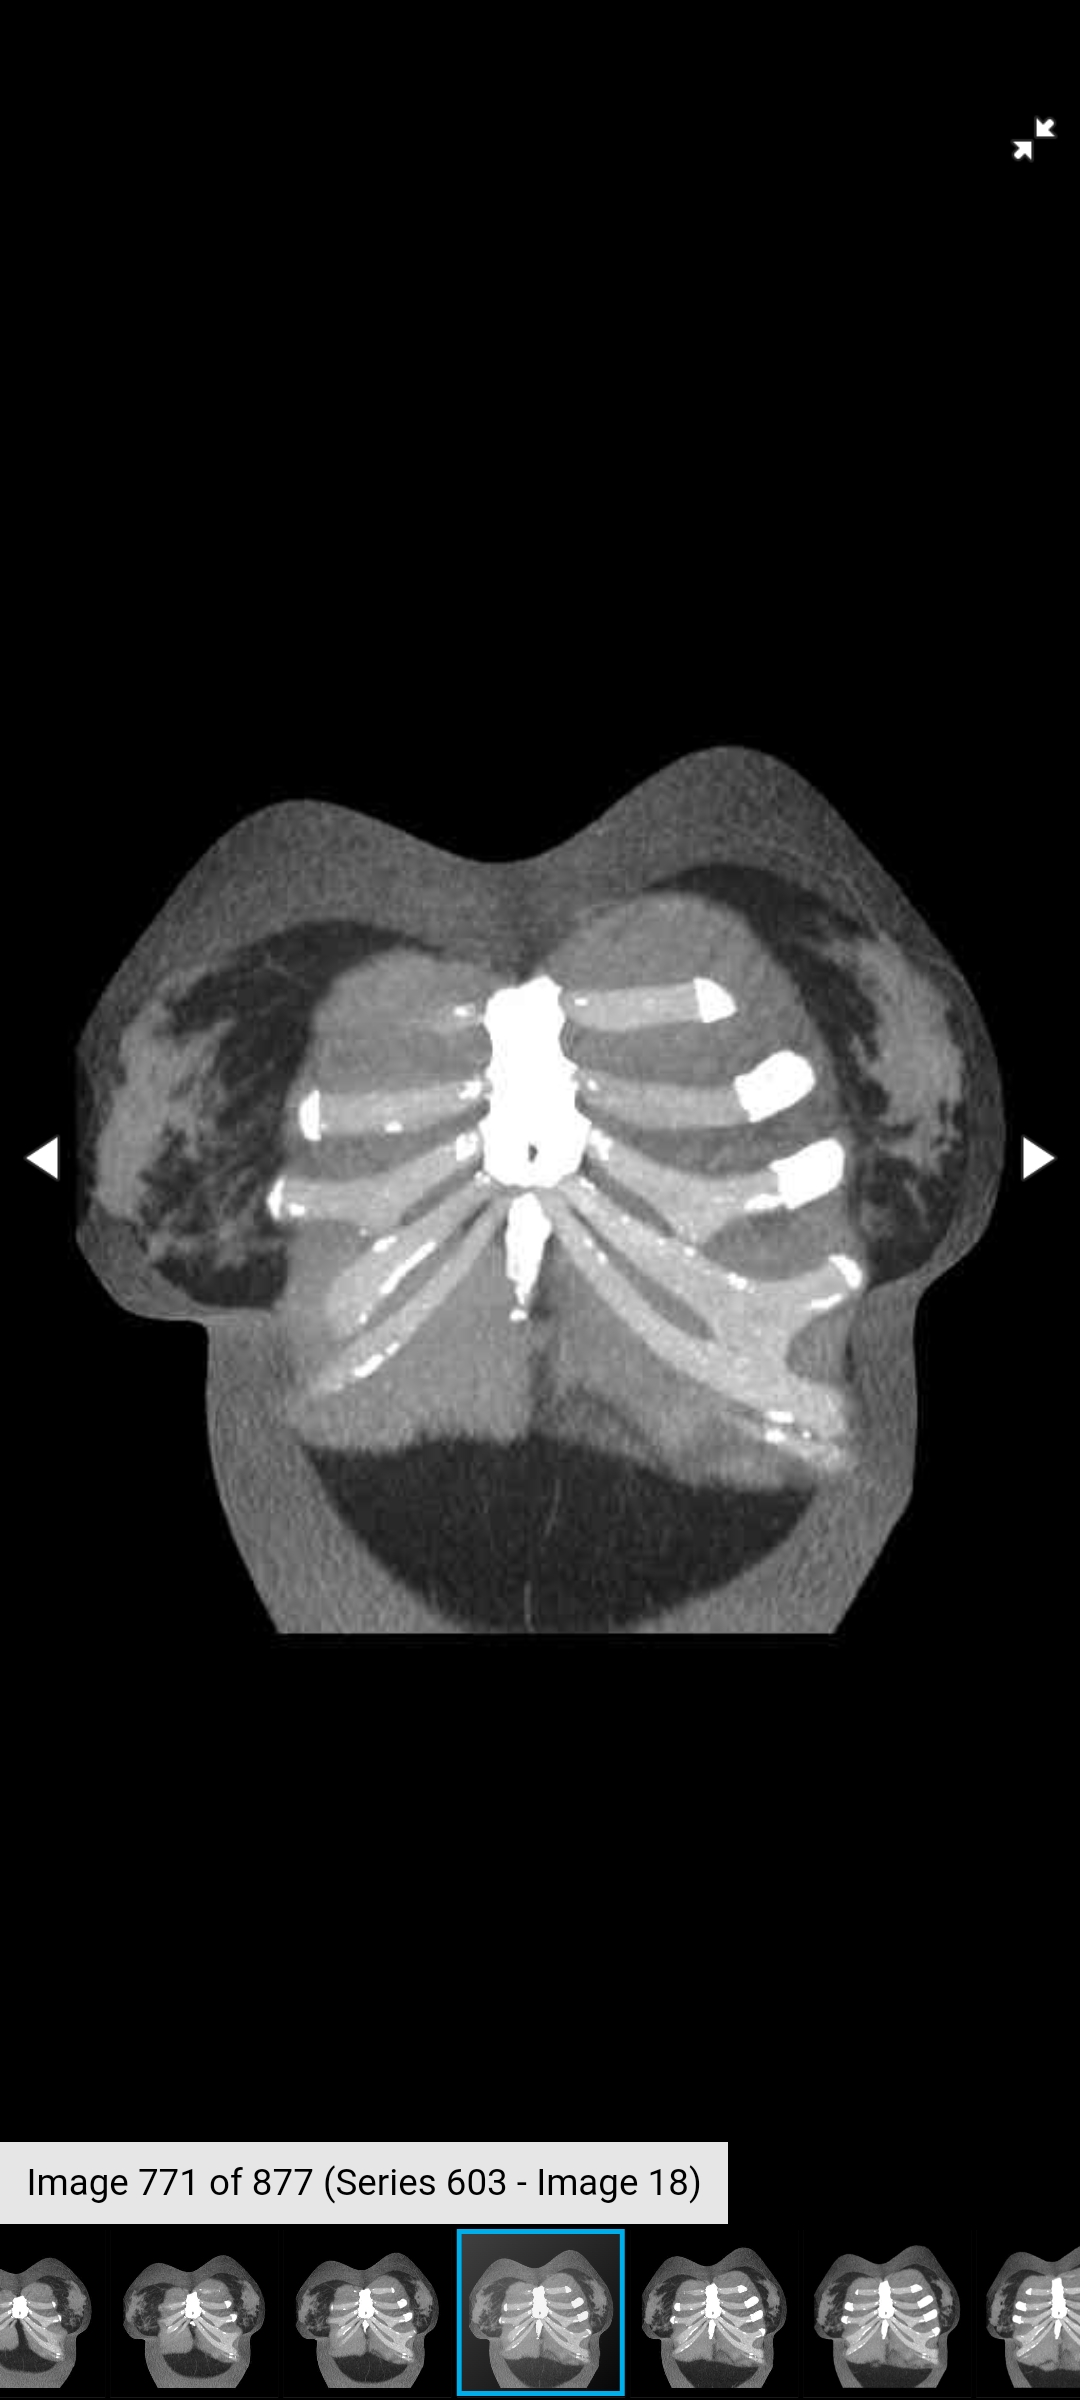

Had to get another CT scan of my ribs for Dr. H. The cover photo for this post is an older CT scan – but you get the idea.

Now, that being said, we think there has been pressure pulling on the higher ribs and that I probably have a bridging cartilage fracture somewhere around my 5/6/7 rib area – last photo for reference. I think it happened when the titanium plate I used to have shifted and I needed it removed, but who knows.